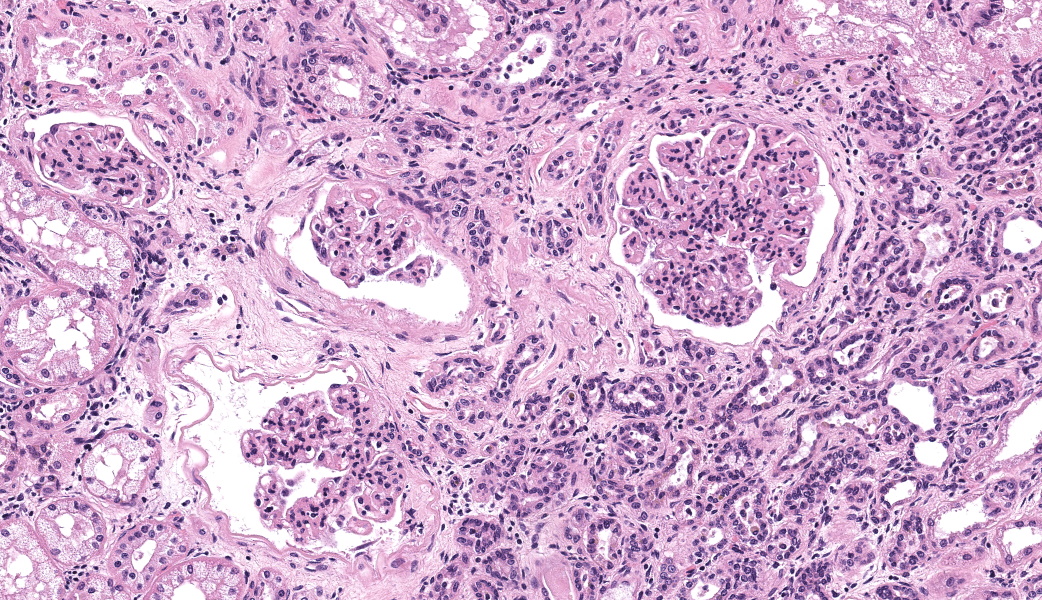

There are multiple sections of kidney that include cortex, medulla, and papilla. All of the glomeruli are affected to varying degrees of severity. The glomeruli are globally hypercellular, within both the endocapillary and mesangial compartments. Capillary walls are markedly thickened by eosinophilic matrix. There is frequent dilation of Bowman’s capsules and segmental collapsed glomerular tufts/ capillaries with expansion of mesangium with eosinophilic matrix (segmental sclerosis). Less than 25% of the glomeruli are globally sclerotic. Occasionally glomerular tufts are segmentally to globally effaced by eosinophilic mesangial matrix, and mesangial and intracapillary dark brown (hemosiderin) and yellow (hematoidin) pigment with scattered hemosiderin laden macrophages within Bowman’s space. There is infrequent segmental loss of podocytes with proliferation of eosinophilic matrix and cells that adhere the glomerular tuft to Bowman’s capsule (crescents). Several glomerular capillary loops are filled with fibrin thrombi.Over half of the tubules are characterized by attenuated epithelium, sloughed hypereosinophilic necrotic intraluminal epithelium, and/or piling of basophilic tubular epithelium (regeneration). Often tubules are dilated with eosinophilic proteinaceous material (hyaline casts), and contain intraluminal basophilic refractile material (mineralization). Infrequently, tubules are filled with degenerate neutrophils. There is a mild loss of tubules with expansion of the interstitium by fibrous matrix and aggregates of lymphocytes with fewer plasma cells. There are multiple arcuate arteries with an expanded tunica intima by increased numbers of smooth muscle cells and fibrous matrix, and/or thickened and hypercellular tunica medias (arteriosclerosis).

Special stains included Masson’s Trichrome, Periodic-Acid Schiff (PAS), and Jones Methenamine Silver (JMS). The PAS demonstrated that the thickened mesangium and glomerular capillary loops were expanded by PAS positive material that often-formed double contours, spike-like projections and encircled bright magenta deposits using the Trichrome stain. Both the PAS and Trichrome highlight the collapsed capillary loops of the globally sclerotic glomeruli with expansion of Trichrome and PAS positive matrix.

Closing out our fourth conference, this case graced participants with an opportunity to see a lovely correlation between light microscopy and electron microscopy (EM) findings. It’s not often that EM images are sent in as part of Wednesday Slide Conference submissions, but it’s always a treat when they are! Many thanks to the contributor for providing both a wonderful slide and beautiful EM images. Together, they truly did paint the whole picture for this EM-worthy condition.Because the EM images were provided, a review of the ultrastructural anatomy of a glomerular capillary profile and its surrounding structures ensued, with focus on the primary and secondary foot processes of the visible podocyte and the different layers of the glomerulus. However, the main show was the electron-dense, granular, irregularly shaped clumps of immune complexes (IC) within subepithelial, intramembranous, and subendothelial spaces of the glomerular tuft. Having IC deposition demonstrably in all three of those locations within the glomerulus assisted with the determination of the “mixed” type of glomerulonephritis in this case. Conference participants favored “membranoproliferative” based on the H&E slide, but acknowledged that this case did not fit 100% into that box upon review of the EM images and accepted the use of the term “mixed” in discussion. Typing of glomerulonephritis is more difficult to do with light microscopy alone due to some histologic similarities between the types, bringing home the point that, for definitive characterization of glomerulonephritis, EM is indispensable.

There was discourse on differentiating membranoproliferative from membranous glomerulonephritis based on histologic features, as some conference participants went one way or the other in their morphologic diagnoses. To summarize, membranoproliferative glomerulonephritis will have an increased number of nuclei within the glomerular tuft, mesangial cell proliferation, and often, the presence of recruited neutrophils. Membranous glomerulonephritis typically just has an increased amount (thickening) of basement membranes. One conference participant inquired on the histologic differences between synechiae and crescents in the glomerulus. Synechiae were described as the touching of the visceral layer of Bowman’s capsule to the parietal layer without fibrosis, whereas crescents have a fibrous component and demonstrate full adhesion of the glomerulus to the capsule. Conference participants did not think there was enough histologic evidence of thrombotic microangiopathy include it in the morphologic diagnosis in this particular case.